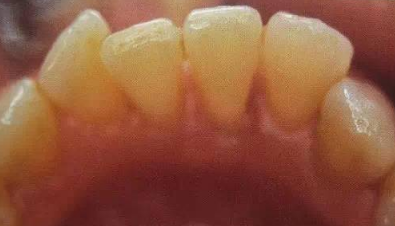

洗牙前后图片对比